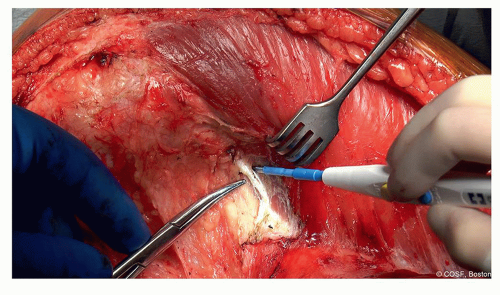

Incise fascia over vastus medialis (Figure 42.5) (

Video)

Keep intact the entire length of wound for later repair

Separate from retinaculum in the distal portion of wound (Figure 42.6) (

Lift medial fascia away from vastus medialis (Figure 42.7) (

Finger dissection with cautery for perforating vessels

Start to release vastus medialis from medial intermuscular septum (Figure 42.8) (

Figure 42-5 ▪ Incising fascia over vastus medialis. (Courtesy of Children’s Orthopaedic Surgery Foundation.)

Figure 42-6 ▪ Separate retinaculum from fascia for double-layered repair later. (Courtesy of Children’s Orthopaedic Surgery Foundation.)

Figure 42-7 ▪ Lift medial fascial flap off vastus medialis. (Courtesy of Children’s Orthopaedic Surgery Foundation.)

Figure 42-8 ▪ Release vastus medialis from intermuscular septum. (Courtesy of Children’s Orthopaedic Surgery Foundation.)

Figure 42-9 ▪ Flex the knee and leave posterior structures free from any pressure. (Courtesy of Children’s Orthopaedic Surgery Foundation.)

Figure 42-10 ▪ Release the distal adductor tendon to enter Hunter canal. (Courtesy of Children’s Orthopaedic Surgery Foundation.)

Figure 42-11 ▪ Release the proximal medial gastrocnemius tendon and muscle to enter the popliteal fossa. (Courtesy of Children’s Orthopaedic Surgery Foundation.)